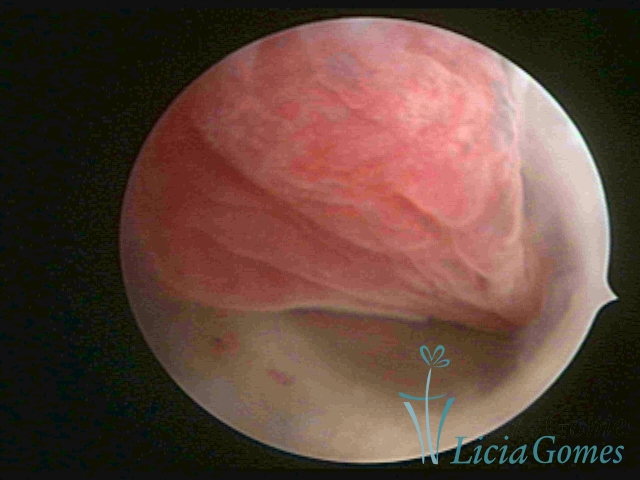

PÓLIPOS ENDOCERVICAIS

São tumores benignos, resultantes da proliferação focal reativa aos processos inflamatórios ou à situações de hiperestrogenismo, e podem ter sésseis (com a base de implantação larga) ou pediculados do epitélio.